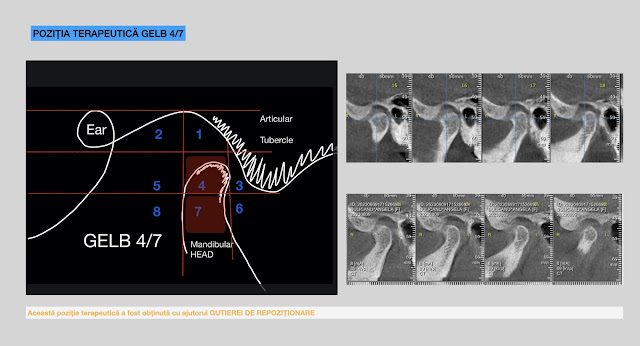

Let’s start with the concept of the HINGE AXIS. We have been taught that the hinge axis is located somewhere in the condyle. If the hinge axis is indeed located within the condyle, then human beings invented the articulator. The articulator replicates the movements and the position of the lower jaw relative to the skull! Working with the articulator is akin to working directly on the human being, given that it replicates the same hinge axis recorded from the patient. After the recording of the hinge axis, we visualize it as depicted in the picture. ONE PROBLEM! Recording the hinge axis on condylography precisely determines the hinge axis. Condylography is a computerized method for determining the hinge axis and tracking the movements of the jaws. After removing the sensors, we can accurately mark the exact location of the hinge axis. CONCLUSION FOR THE RIGHT JOIN: The hinge axis is located at the margin of the external ear duct. While we were taught that the anatomical hinge axis is ty...